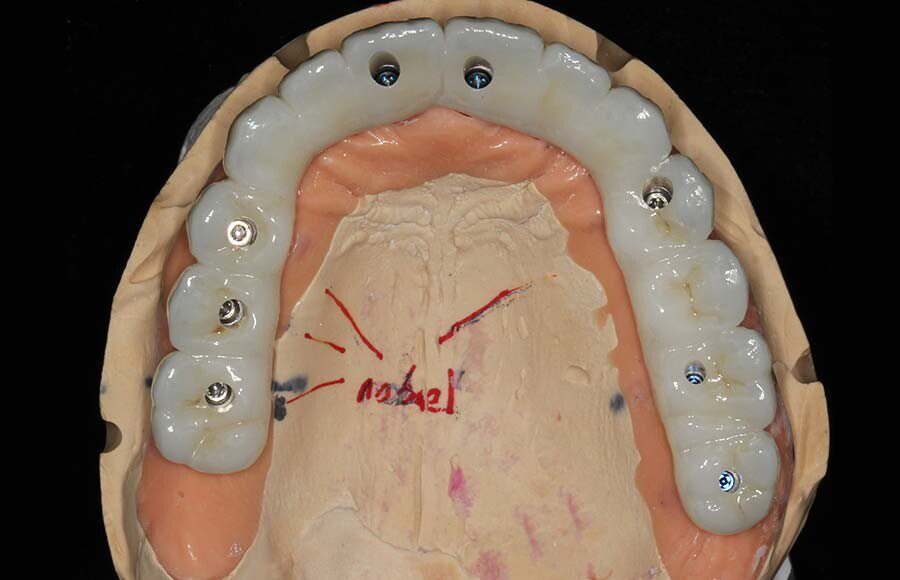

Smile GalleryImplant RestorationsFull Mouth Implant Restoration Full arch zirconia implant bridge (full smile) 1 of 37 Pre-op full smile Pre-op lips retracted Pre-op panoramic x-ray Extraction of strategic teeth Placement of implants Extraction of some remaining teeth after verification of adequate implant stability Occlusal view Post-op panoramic x-ray Immediately fabricated provisional restoration (tissue side view) Immediately fabricated provisional restoration (occlusal side view) Immediate provisional delivered on day of surgery Immediate provisional 2 weeks later Scalloped tissue developed from the provisional at 2 weeks Jig used for making a master impression Provisional in place (full smile) Provisional in place (lips retracted) Provisional in place (right side) Provisional in place (left side) Wax try-in (full smile) Wax try-in (right side full smile) Wax try-in (left side full smile) Wax try-in (full face, lips together) Wax try-in (full smile) Wax try-in (right side) Wax try-in (left side) Wax try-in (lips retracted) Full arch zirconia implant bridge on master cast (frontal view) Full arch zirconia implant bridge on master cast (occlusal view) Implant positions and soft tissue representation on master cast (occlusal view) Soft tissue representation on master cast (frontal view) Full arch zirconia implant bridge (tissue side view) Soft tissues on day of delivery (occlusal view) Soft tissues on day of delivery (frontal view) Full arch zirconia implant bridge delivered (lips retracted) Full arch zirconia implant bridge (lips retracted, close up) Post treatment panoramic x-ray Full arch zirconia implant bridge (full smile)